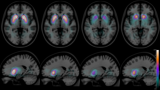

放射性标记抗体的功能化以增强高对比度脑成像的外周清除率

早在2 年前,正电子发射断层扫描 (PET) 药物 [11C]Pittsburg compound B ([11C]PiB),因其与活脑种淀粉样蛋白-β (Aβ) 斑块的结合与可视化,为阿尔茨海默病 (AD)的研究和诊断提供了新的研究方向。然而,进一步的研究表明,在疾病进展过程中,放射性示踪剂的脑滞留保持静止,并且特定APP突变携带者以及Aβ斑块主要弥漫的AD患者的Aβ病理学无法用该方法观察。 2023-02-16 PET/CT放射性示踪剂